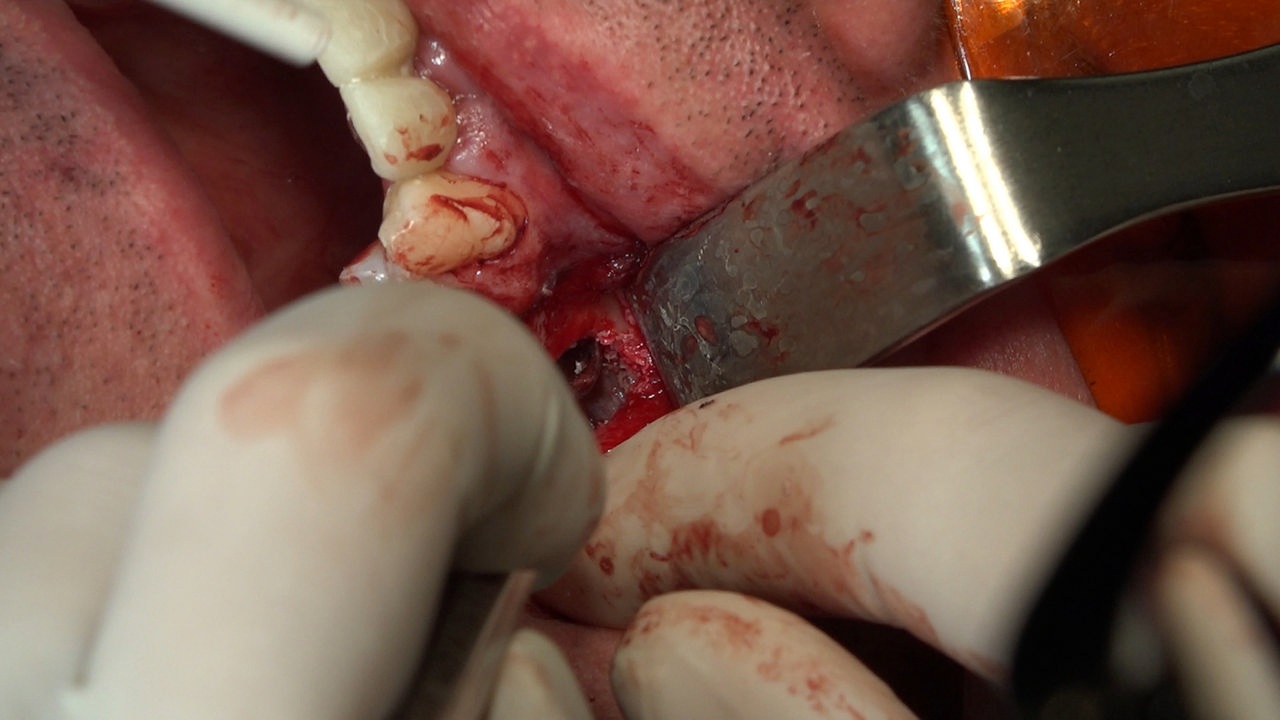

PRACTICULUM IMPLANTOLOGII - SEZON X - SESJA 7

7 Sesja X Sezonu Practiculum Implantologii, w której brali udział kursanci z Grupy A i B, obejmowała implantacje wykonane systemem Axiom, procedury regeneracyjne tkanki kostnej i zabieg sinus lift oraz procedury implantoptotetyczne. Ten zakres szkolenia poprowadziła dr Małgorzata Piotrowska. Protetyka na implantach, to finalny etap leczenia implantologicznego decydujący o uzyskaniu harmonijnego łuku zębowego, okluzji oraz szczelności połączeń, a więc zadowoleniu Pacjenta i powodzeniu całego procesu leczenia.